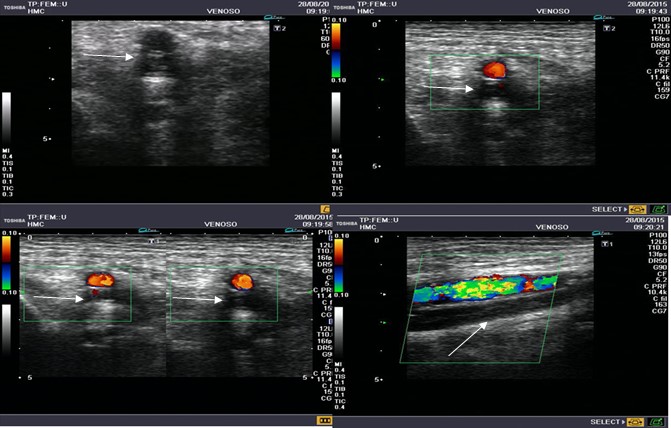

El diagnóstico de TVP se realiza en modo B, median-te compresiones intermitentes cada 2 o 3 cm en el eje transverso y en todo el trayecto del vaso. No debe realizarse en el eje longitudinal debido a que las venas pueden desplazarse fuera del plano de la imagen y simular que se ha comprimido.

Esta se determina según el tiempo de evolución en relación a la visualización con DC (9, 10) (Fig. 7, Fig. 8).

TVP aguda

Hallazgos en la imagen con modo B:

- Baja ecogenicidad.

- Distensión venosa.

- Pérdida de compresibilidad.

- Trombo que flota libremente: cuando se observa esta imagen no se debe manipular distalmente porque este es potencialmente embolígeno.

Anomalías en la señal DC:

- Ausencia de flujo proximal al segmento trombosado.

- Distal al mismo se observa flujo continuo, con ausencia de variabilidad respiratoria.

- Colateralización: las venas colaterales aumentan rápidamente de tamaño durante la fase aguda.

- Las imágenes con flujo color se realizan en el eje largo paralelo a las venas.